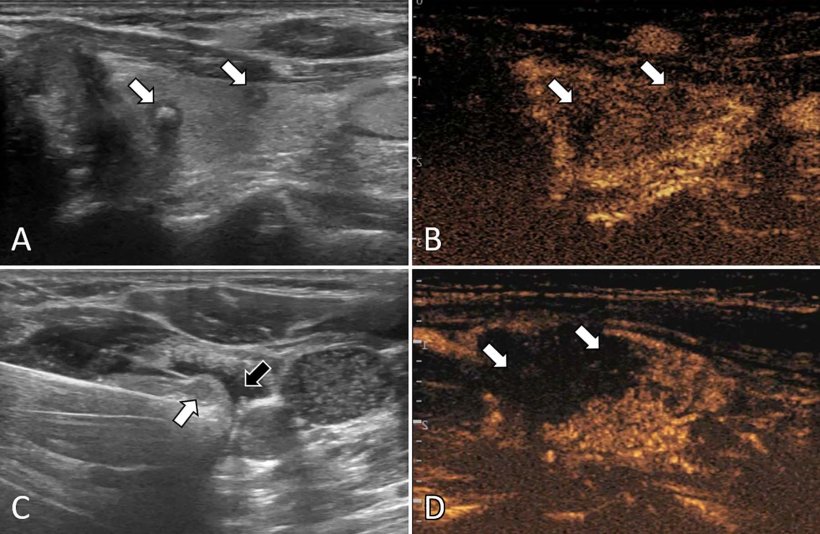

Медицина и диагностика: Инвазивный пузырный занос на УЗИ

Раздел: Альбом идей